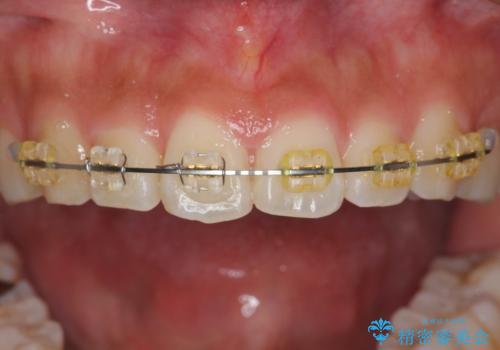

- 前歯の目立つねじれを矯正治療で治したい、と来院されました。

マウスピース矯正を始める前に、ねじれを取るのが短期間で済む部分ワイヤー小矯正を行うことで、全体的な治療期間を短くする治療計画を実行していきます。

前歯のねじれはマウスピース矯正の苦手な動きになり、治療期間が長くなる原因になりやすいです。